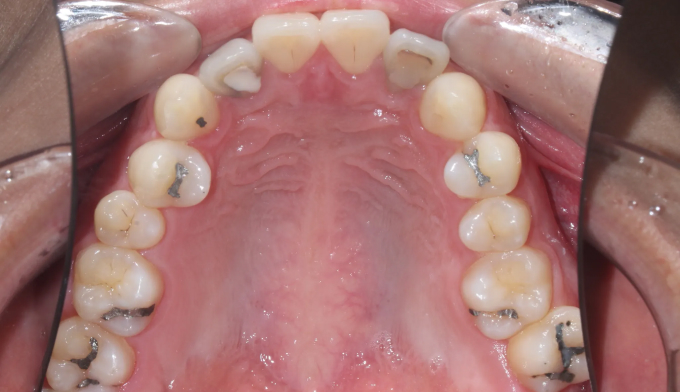

돌출감과 가지런하지 못한 앞니, 그리고 어금니의 교합이 좋지 않은 경우입니다.

좌측 아래 작은어금니가 빠진이 오래되었기 때문에, 균형을 맞추기 위해 반대편 작은어금니를 발치하여 돌출감을 해소해주었습니다. 나왔던 입이 들어가면서 턱 라인이 개선되었고, 입을 다물때도 보다 더 편안하게 되었습니다.

교정전부터 변색되어있던 양쪽 앞니는 미백과 보철치료를 동반하여 교정종료 후 개선하였습니다.